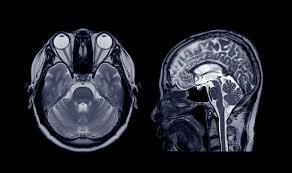

- RMN CEREBRAL

Diagnosticul tumorilor în special al celor de dimensiuni mici, exemplu: neurinom de nerv acustic, adenom hipofizar, metastaze.

Afecţiuni inflamatorii: ex scleroza multiplă.

Diagnosticul AVC.

Afecţiuni vasculare, ex. tromboza sinusurilor venoase.

Procese tumorale ale fosei posterioare.

Afecţiuni degenerative.

RMN - angiografie.

Diagnosticul complicaţiilor infecţiei HIV.

Malformaţii congenitale cerebrale.

Diagnosticul hidrocefaliei.

Diagnosticul afecţiunilor sinusurilor paranazale.

Examinarea orbitei şi a globului ocular (tumori, inflamatii), aprecierea muşchilor globilor oculari şi a nervilor optici.

RMN permite obţinerea unor imagini multiplanare din organismul uman, fără utilizarea razelor X (Roentgen), făcând posibilă diagnosticarea cu precizie a numeroase afecţiuni. Astfel se obţin imagini sub formă de secţiuni în orice plan de coordonate.

Investigaţia vizualizează până la cele mai mici detalii morfologice, ţesuturi din organe (creier, coloană vertebrală, articulaţii, uetre, vezică urinară etc.), nervi sau structuri vasculare fine, tumori etc., astfel putându-se depista leziuni foarte mici de până la 2mm.